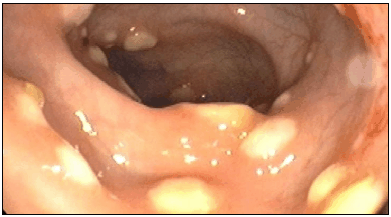

A colonização gastrointestinal causada por esse agente, uma bactéria anaeróbia obrigatória, é observada em, aproximadamente, 20% dos pacientes com período de internação hospitalar superior a uma semana.

Sobre o agente etiológico mais comumente causador da lesão observada na colonoscopia, é correto afirmar que: